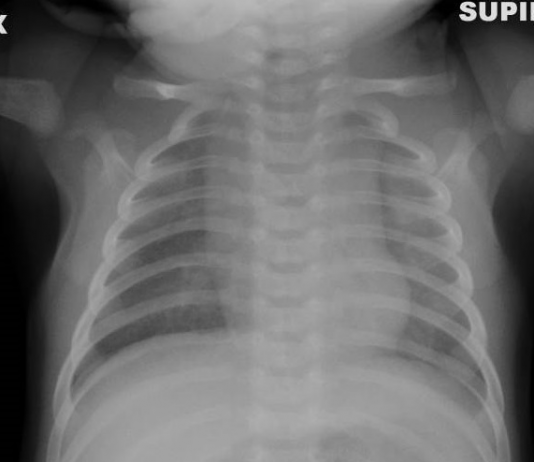

F.Finazzo , G Paviglianiti, M.P.Pappalrdo UOC Radiologia Pediatrica PO G.DI Cristina Arnas Civico Palermo Direttore Dott.ssa M.P. Papplardo

Bimbo di tre mesi ,fratello Covid -19 positivo e genitori Covid-19 positivi ,sintomatici in quarantena presso il loro domicilio.

Viene portato...